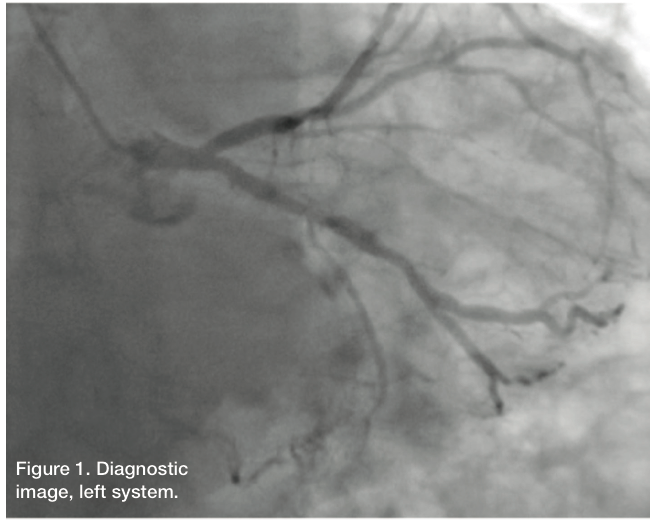

Left main: The left main is calcified. It is patent. It bifurcates into the left anterior descending coronary artery and circumflex artery.

Left circumflex (LCX): The LCX is calcified. It is patent. It gives rise to the atrioventricular (AV) groove with a large obtuse marginal that bifurcates.

Left anterior descending coronary artery (LAD): The LAD is a calcified vessel. There is approximately 40% proximal/mid stenosis involving the first septal. The remaining mid and distal LAD has mild luminal irregularities, with a mid 30%-40% stenosis.

Right coronary artery (RCA): The RCA is 100% occluded. It is diffusely diseased in its proximal and mid portion with mid 100% occlusion. There is evidence of left to right collaterals.

Ejection fraction: 50 to 55%, with some mild inferior wall hypokinesis.